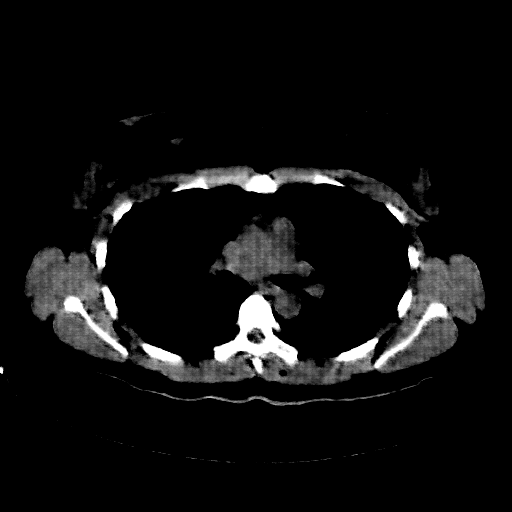

Image Grid

4Γ—3 grid: Rows show different image types (Original NATIVE, Reconstructed NATIVE, Original VENOUS, Generated VENOUS), Columns show windowing techniques (No Window, Lung Window, Mediastinum Window)

Generated VENOUS CT scan (A→B translation)

Full window (WL 1023.5, WW 4095 β†’ Low βˆ’1024, High +3071)

Lung window (WL -600, WW 1500 β†’ Low βˆ’1350, High +150)

Mediastinum window (WL 40, WW 400 β†’ Low βˆ’160, High +240)